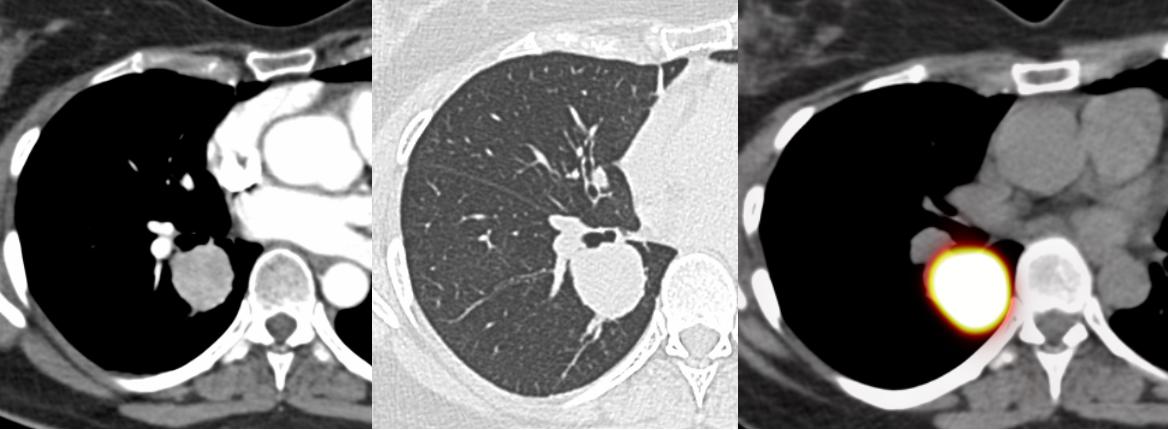

A 50-years old had a nodule in the right lower lobe that was DOTA-PET/CT positive.

Both lesions are highly suggestive of a well-differentiated neuroendocrine tumor (NET)/carcinoid. One patient went straight to surgery while another still underwent a biopsy and then surgery.